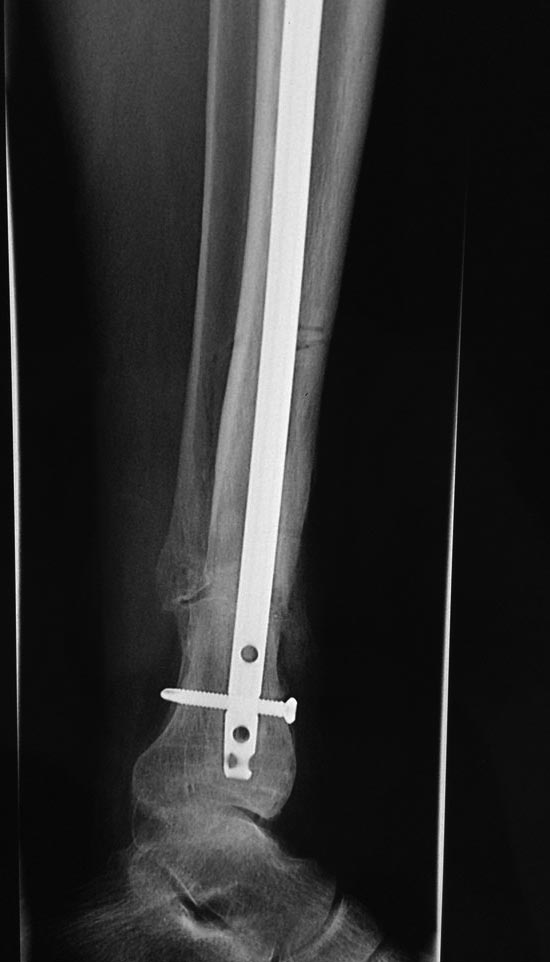

Уважаемые коллеги выразите Ваше мнение по следующему случаю. Молодой

человек, 27 лет, находится на лечении с диагнозом: Ложный сустав

большеберцовой кости в нижней трети, фиксированный интрамедуллярным

блокированным стержнем (12.02.2014 г), ложный сустав малоберцовой кости

в нижней трети левой голени, посттравматический артроз левого

голеностопного сустава 1 стадии. Укорочение левой нижней конечности на

В феврале 2014 г выполнил первым этапом: Фиксацию ложного

сустава в АНФ с восстановлением осей сегментов. Через семь дней БИОС с

рассверливанием.

После операции - вальгус голеностопного сустава. Гладкое течение

послеоперационного периода. Нагрузка по переносимости боли. Через 6

недель динамизация, через 2 недели стали мигрировать 2 фронтальных

винта. Пытался подкрутить, пришлось удалить.